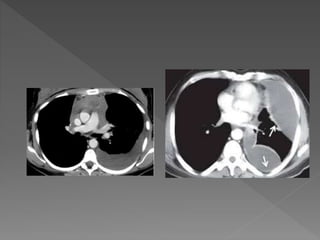

CT thorax

 Useful if effusion is minimal or loculated

 to differentiate effusion from pleural thickness

Ultrasound  Helps todifferentiate consolidated lung from pleural fluid especially when there is white out on CXR and clinical signs do not clearly distinguish  Identify pleural thickening and loculated effusions  To guide thoracocentesis and chest tube insertion CT thorax  Useful if effusion is minimal or loculated  to differentiate effusion from pleural thickness